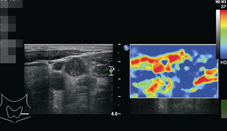

回顧近五年來超音波檢查的最新進展為彈性超音波的發展,彈性超音波原理是利用組織對壓力會產生應力的改變的原理 (strain,即組織的位移,代表軟硬度),臨床上經由超音波探頭的壓迫,以及用音波反射來評估應力的改變,(應力的改變較大表示較軟,通常以紅色或綠色表現,應力的改變較小表示較硬,通常以藍色表現,圖三),惡性腫瘤的硬度較硬,彈性超音波已被證實對於軟組織腫瘤,如:乳癌、甲狀腺癌、惡性淋巴腫的評估很有幫助。

圖三、新一代彈性超音波原理是利用組織對壓力會產生應力的改變的原理 (strain,即組織的位移,代表軟硬度),臨床上經由超音波探頭的壓迫,以及用音波反射來評估應力的改變,(應力的改變較大表示較軟,通常以紅色或綠色表現,應力的改變較小表示較硬,通常以藍色表現),彈性超音波對於惡性腫瘤的評估很有幫助。